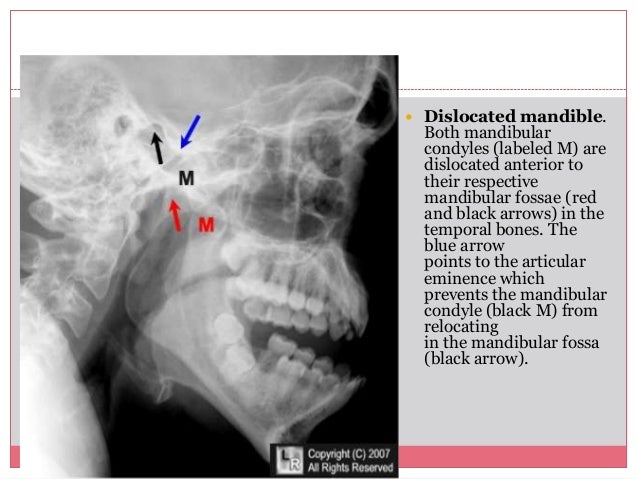

Cntuk Cntuk mengu menguran rangi gi sensasi nyeri relasksasi, latihan nafas dalam, imajinasi 6isualisasi, sentuhan “. Peng Pengka kaji jian an pri prime mer: LP Fraktur Humerus fraktur humerus. Lp Fraktur Depressed fraktur depresiFull description. Nursing actions performed by nurses that assess pain in a comprehensive manner, including the location, characteristics, frequency, quality and precipitation factors, Teach and encourage the management of pain relaxation breath inmonitor vital signs and general state of the client, keep the immobilization on the sick, collaboration with doctor of analgesics and implement treatment programs doctor, assess client personal hygiene, help clients to meet the needs of personal hygiene, help clients ADL fulfillment.ĭESIGN OF STRUCTURAL ELEMENTS W.M.C.MCKENZIE PDF Cntuk Cntuk mence mencegah gah dekubitus A. Your consent to our cookies if you continue to use this website. Cntuk Cntuk menc mencega egah h infek infeksi si antibiotik. Lp Fraktur Radius Ulna lp fraktur radius ulna. LP Fraktur Femur laporan pendahuluan fraktur femurDeskripsi lengkap. Clients suffering from mandibular keperawataan have a problem of basic human needs are acute pain associated with physical injury agents Objective: More information and software credits. LP Fraktur Femur Dextra laporan pendahhuluan fraktur fmur dextra beserta askepnya. Pertahankan Pertahankan imobilisasi bagian bagian Rasiona ‘. The nursing diagnoses were acute pain associated with physical injury agents and self-care deficits associated with weakness.

A () ASUHAN KEPERAWATAN PEMENUHAN need, mandibular fractures rasa aman dan nyaman, fraktur mandibula. Askep Dm Fqh askep dm Askep Dm Gizi Diet Kel 3 ASKEP DM askep dm ASKEP DM KGD II ASKEP DM Askep Fraktur Mandibula.